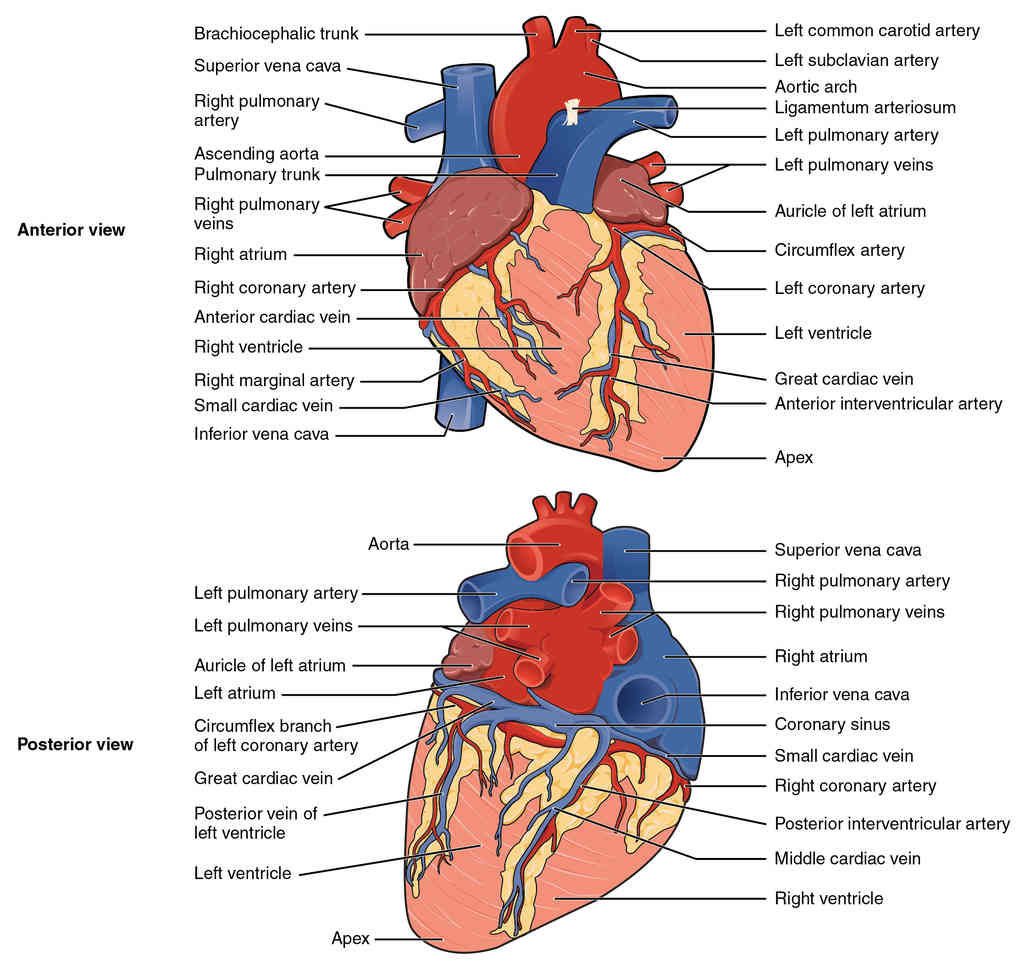

This page is under construction. For now, it is just a resource of the images found in the OpenStax Anatomy and Physiology Handbook. It wil slowly change into a revision tool. Each slide has a number. Use this to refer to the slide. When completed, it will have an unlabelled section, with labelled slides in parallel. On the unlabelled slides, write your answer and use the labelled slide to assess yourself. Keep track by also noting the number on each slide. Improvement at each attempt is important, more so than full marks on a first attempt.